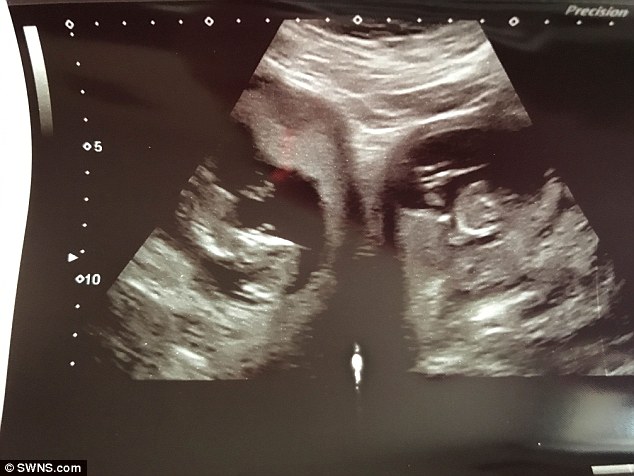

Эцэг эхүүдийн хувьд ихэр хүүхэдтэй болно гэдэг нь маш гайхалтай гэнэтийн бэлэг гэж хэлж болно. Женнифер Эшвуд гэх британи эмэгтэйн хувьд ихэр хүүхэдтэй болсон мэдээнээс гадна өөр нэгэн давхар гэнэтийн мэдээ сонсжээ.

Түүнийг бие давхар байх үед эмч нар хоёр савтай бөгөөд сав тус бүр нэг хүүхэд байгааг олж мэджээ. Энэ нь 500 саяд нэг тохиох тохиолдол аж. Ихэнх эмэгтэй жирэмсэн байхдаа нэг саванд нэг л хүүхэд тээдэг. Эшвудын хувьд найман жилийн өмнө нэг охин төрүүлсэн бөгөөд энэ удаад маш сонирхолтой тохиолдолоо ихэр хүүхэдтэй болжээ. Хэдийгээр энэ гэр бүлд сонирхолтой төрөлт байсан ч дутуу төрөх эсвэл зулбах эрсдэл байсан учир байнгын эмчийн хяналтанд байжээ. Эшвуд жирэмсэний 34 дэх долоо хоногтоо Пиран болон Поппи гэх эрэгтэй, эмэгтэй ихрүүдээ төрүүлсэн байна.